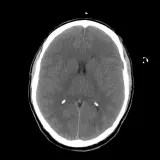

Over 2,100 interactive radiology cases, curated by radiologists for your level of training. Scroll, window, and view cases full screen — just like on PACS. Click linked findings in each writeup to jump straight to them on the image. Cases include sample reports, a focused discussion section, original illustrations, and videos.

完全交互式病例,配备您在 PACS 上期待的各项工具——滚动、调窗、缩放、平移、测量、ROI 和全屏模式。

丰富的标注直接在病例图像上突出关键发现。点击病例讲解中的关联发现,即可跳转至其在扫描上的精确位置。